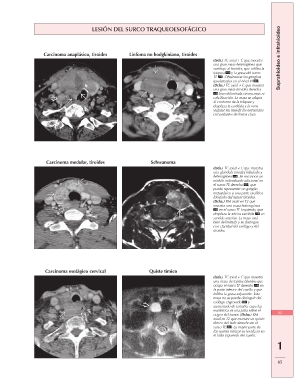

LESIÓN DEL SURCO TRAQUEOESOFÁGICO Suprahioideo e infrahioideo

Carcinoma anaplásico, tiroides Linfoma no hodgkiniano, tiroides

(Izda.) TC axial + C que muestra

una gran masa heterogénea que

sustituye al tiroides, que infiltra la

tráquea y la grasa del surco

TE . Obsérvense los ganglios

ipsolaterales en el nivel VI .

(Dcha.) TC axial + C que muestra

una gran masa tiroidea derecha

bien delimitada sin necrosis ni

calcificación. La masa se adapta

al contorno de la tráquea y

desplaza la carótida y la vena

yugular sin invadir las estructuras

circundantes de forma clara.

Carcinoma medular, tiroides Schwanoma

una glándula tiroides lobulada y

heterogénea . Se reconoce un

nódulo redondeado adicional en

el surco TE derecho , que

puede representar un ganglio

metastásico o una parte exofítica

lobulada del tumor tiroideo.

(Dcha.) RM axial en T2 que

muestra una masa heterogénea

en el surco TE izquierdo, que

desplaza la arteria carótida en

sentido anterior. La masa está

bien delimitada y se distingue

con claridad del esófago y del

tiroides.

Quiste tímico

(Izda.) TC axial + C que muestra 65

una masa de tejidos blandos que

ocupa el surco TE derecho en 1

la parte inferior del cuello y que

infiltra la grasa adyacente. Esta 65

masa no se puede distinguir del

esófago engrosado y

aumentado de tamaño, cuya luz

excéntrica es una pista sobre el

origen del tumor. (Dcha.) RM

axial en T2 que muestra un quiste

tímico del lado derecho en el

surco TE . La mayor parte de

los quistes tímicos se localizan en

el lado izquierdo del cuello.